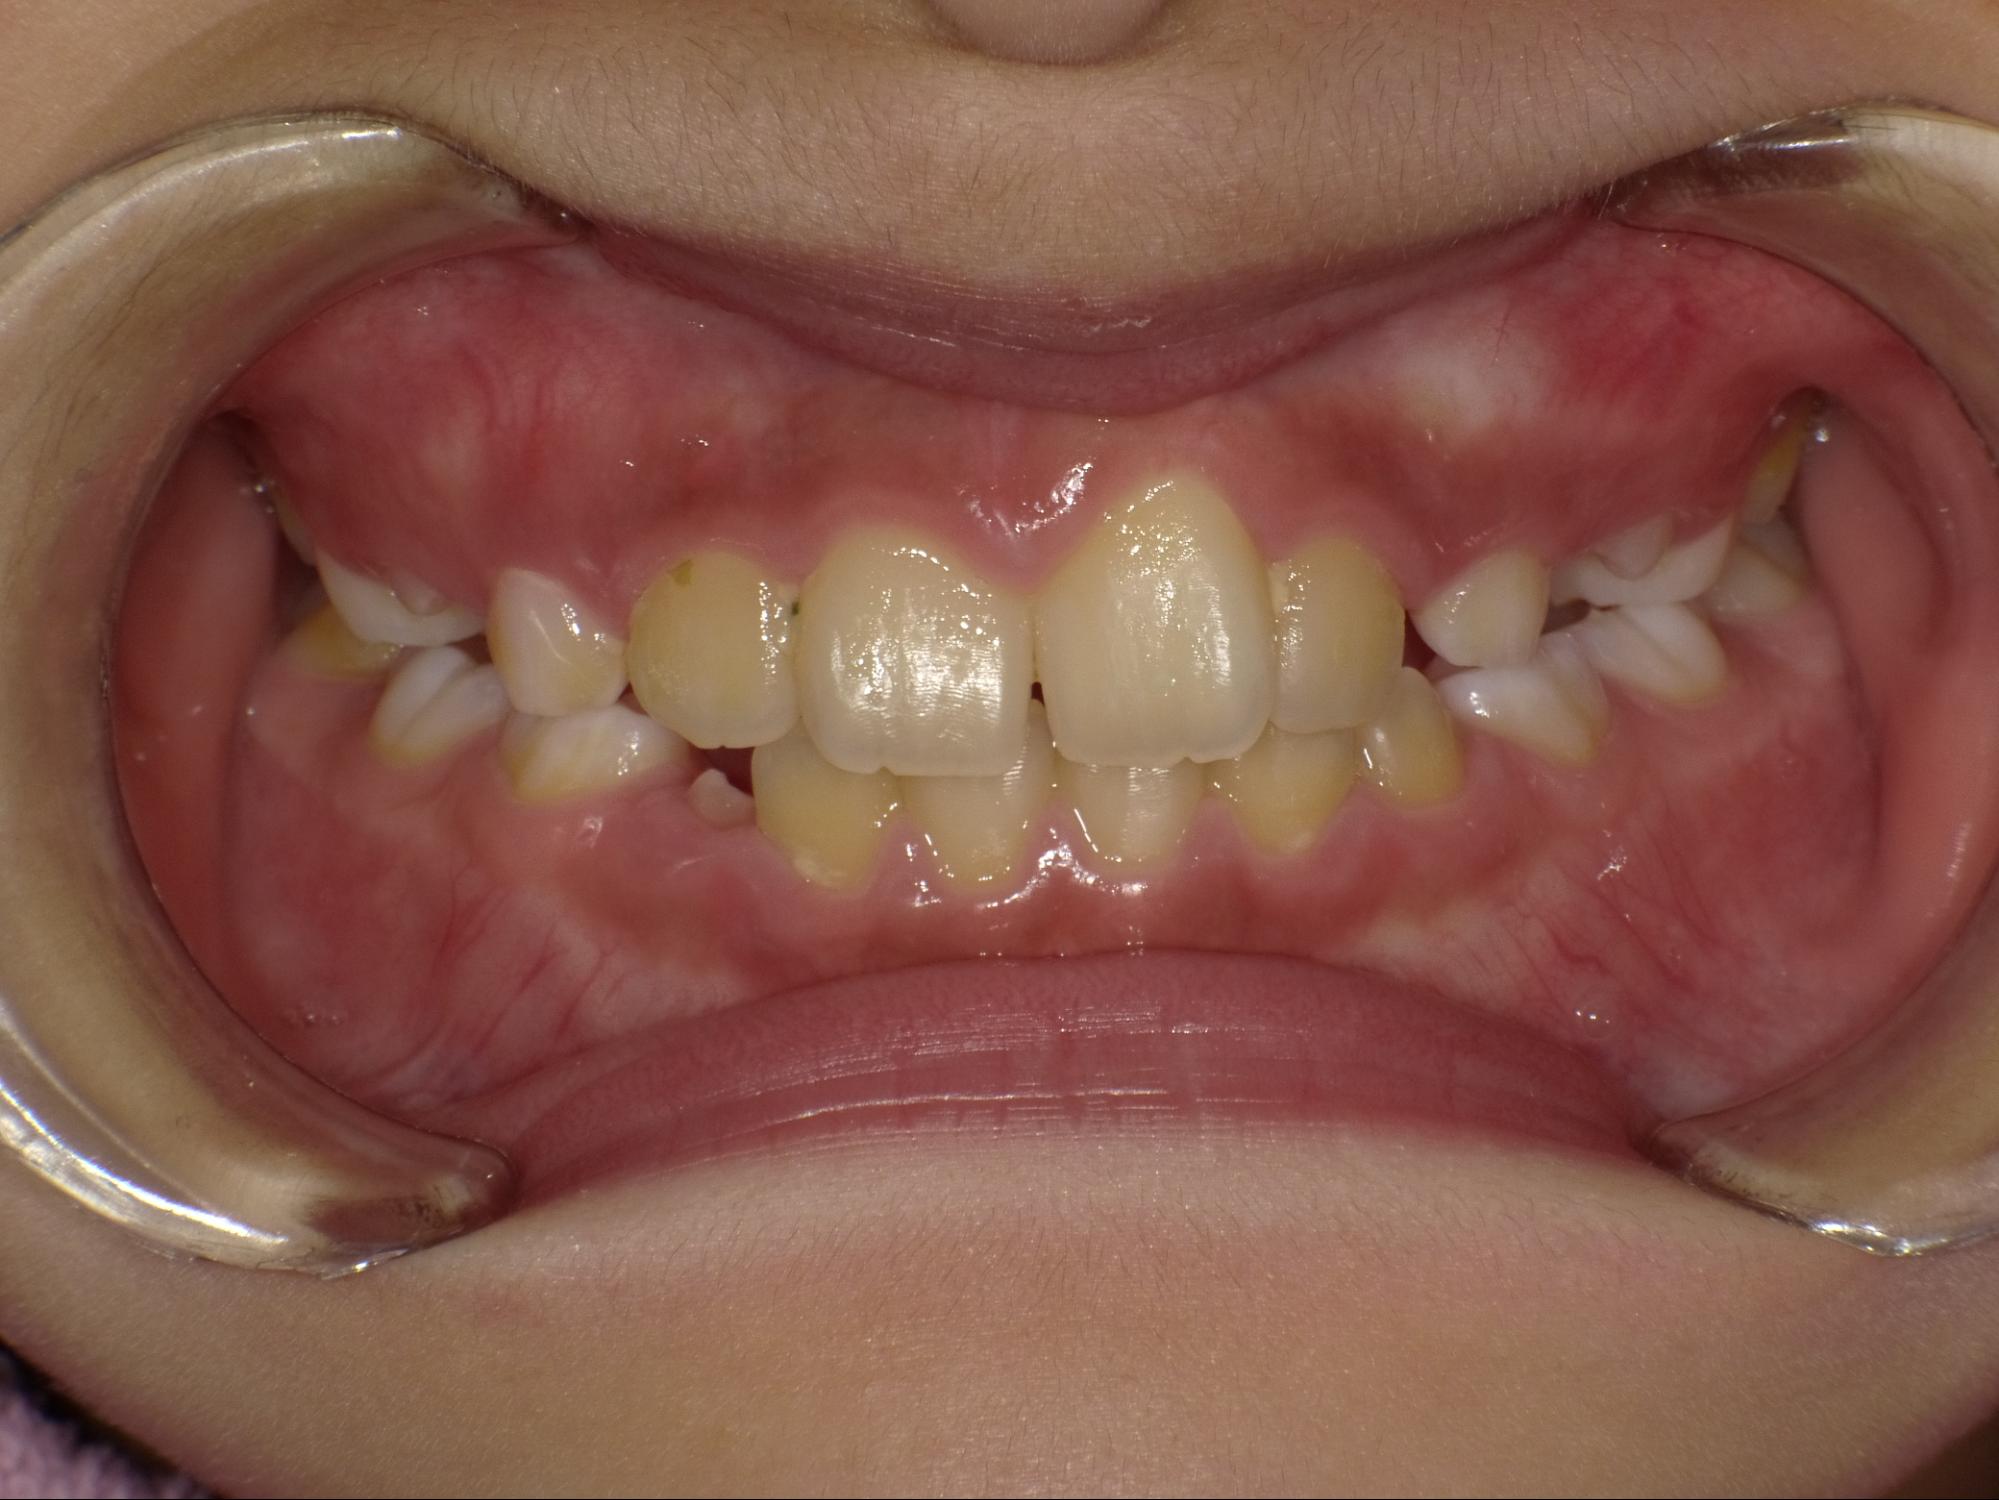

| 年齢・性別 | 8歳9ヶ月の男児 |

|---|---|

| 主訴 | 前歯の咬み合わせが逆になっており、歯根や歯肉への影響を懸念されて来院された患者様です。 |

| 治療期間・回数 | 3年7ヶ月・20回 |

| 費用 | 460,000円(税別) |